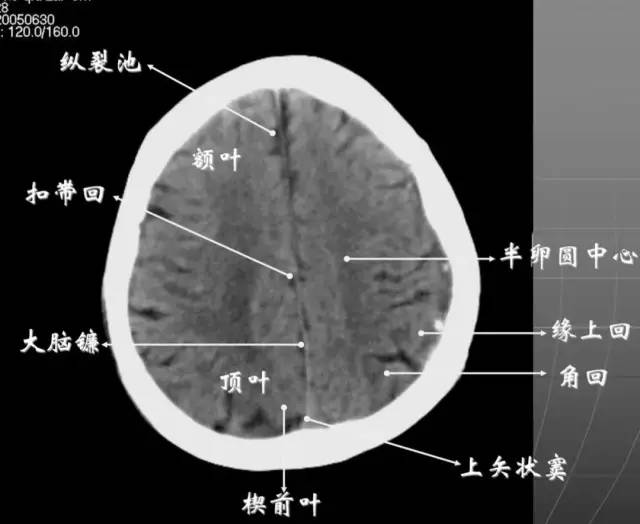

7、大脑皮质下部层面(半卵圆中心层面)在胼胝体和侧脑室上方,大脑镰自前向后贯穿中线。白质部分为半卵圆中心,额叶范围缩小,顶叶所占比例扩大,枕叶基本消失。

半卵圆中心:位于胼胝体上方,由左右大脑半球髓质形成的有髓纤维,对称位于大脑镰两侧区域。

8、大脑皮质上部层面(半卵圆区上部层面)已近颅顶,大脑镰清晰可见,其旁的脑灰质和脑沟十分清楚。顶叶较小,额叶较小。

放射冠:是内囊到大脑皮质间的放射状纤维白质。